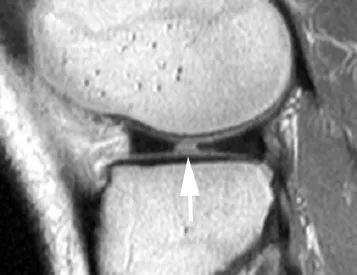

Прерывистый или усеченный вид мениска-бабочки на сагиттальном изображении (рис. 6);

Рис. 6. Радиальная щель в переднем сегменте медиального мениска в сагиттальной проекции, взвешенной по протонной плотности.Нормальный вид усеченной бабочки медиального мениска (стрелка).